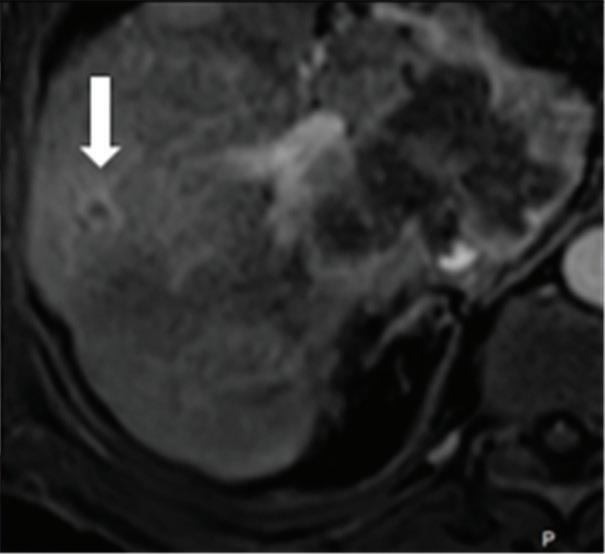

Multifocal HCC treated with sorafenib. (a) A small nodule (arrow) is barely seen on conventional axial CT image, acquired at late arterial phase after administration of 70 ml of contrast material (iodine concentration 350 mg/ml). (b) Monoenergetic 50 keV and (c) Z effective images improve the detection of this small nodule as well as allowing better evaluation of the peripheral solid component of both nodules seen in these images, with a precision comparable to that of (d) post contrast MR image.

Liver tumors. Use of low-monoenergetic images on late arterial phase improves the detection of hypervascular liver lesions (e.g., HCC in cirrhotic liver) (Figure 4).3,17,52,53 It also improves detection of hypovascular liver metastases on portal-venous-phase.54